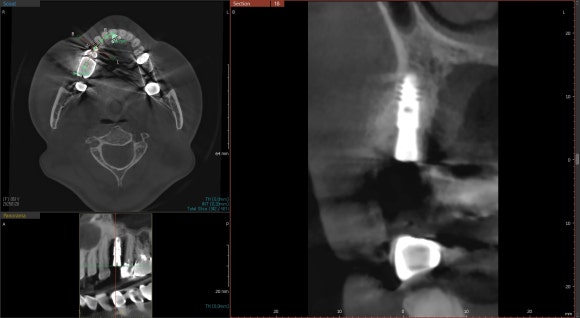

20240120

치아를 둘러싼 염증이 심하신 편이 아니어서

(=깨끗하고 감염이 없는 뼈조직)

치아를 발치하면서 동시에

임플란트를 식립하였습니다.

뼈가 얇고 좁은 환자분들은

시간이 지남에 따라 뼈가 흡수되어

주저앉는 경우가 많기 때문입니다.

수술 후 반드시 CT를 촬영하여

원하는 위치에, 원하는 방향으로

임플란트가 제대로 식립되었는지

확인하는 것이 중요합니다.

눈으로 볼 수 없는 곳까지

꼼꼼하게 체크하는 과정입니다.

임플란트를 원하는 위치에 정확히 식립하는 것은

술자의 경험과 공간지각력에 의해

크게 좌우됩니다.